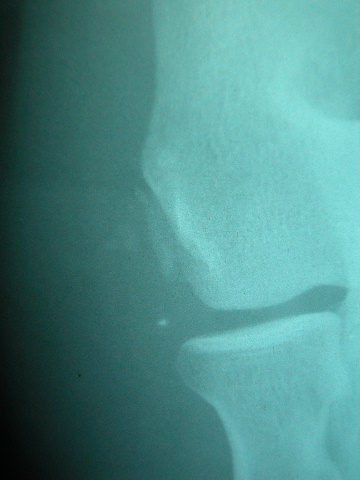

Fractura supracondílea de codo.

Fractura supracondílea de codo.Tras reducción y osteosíntesis.

Fractura supracondílea de codo. Tratamiento con agujas.